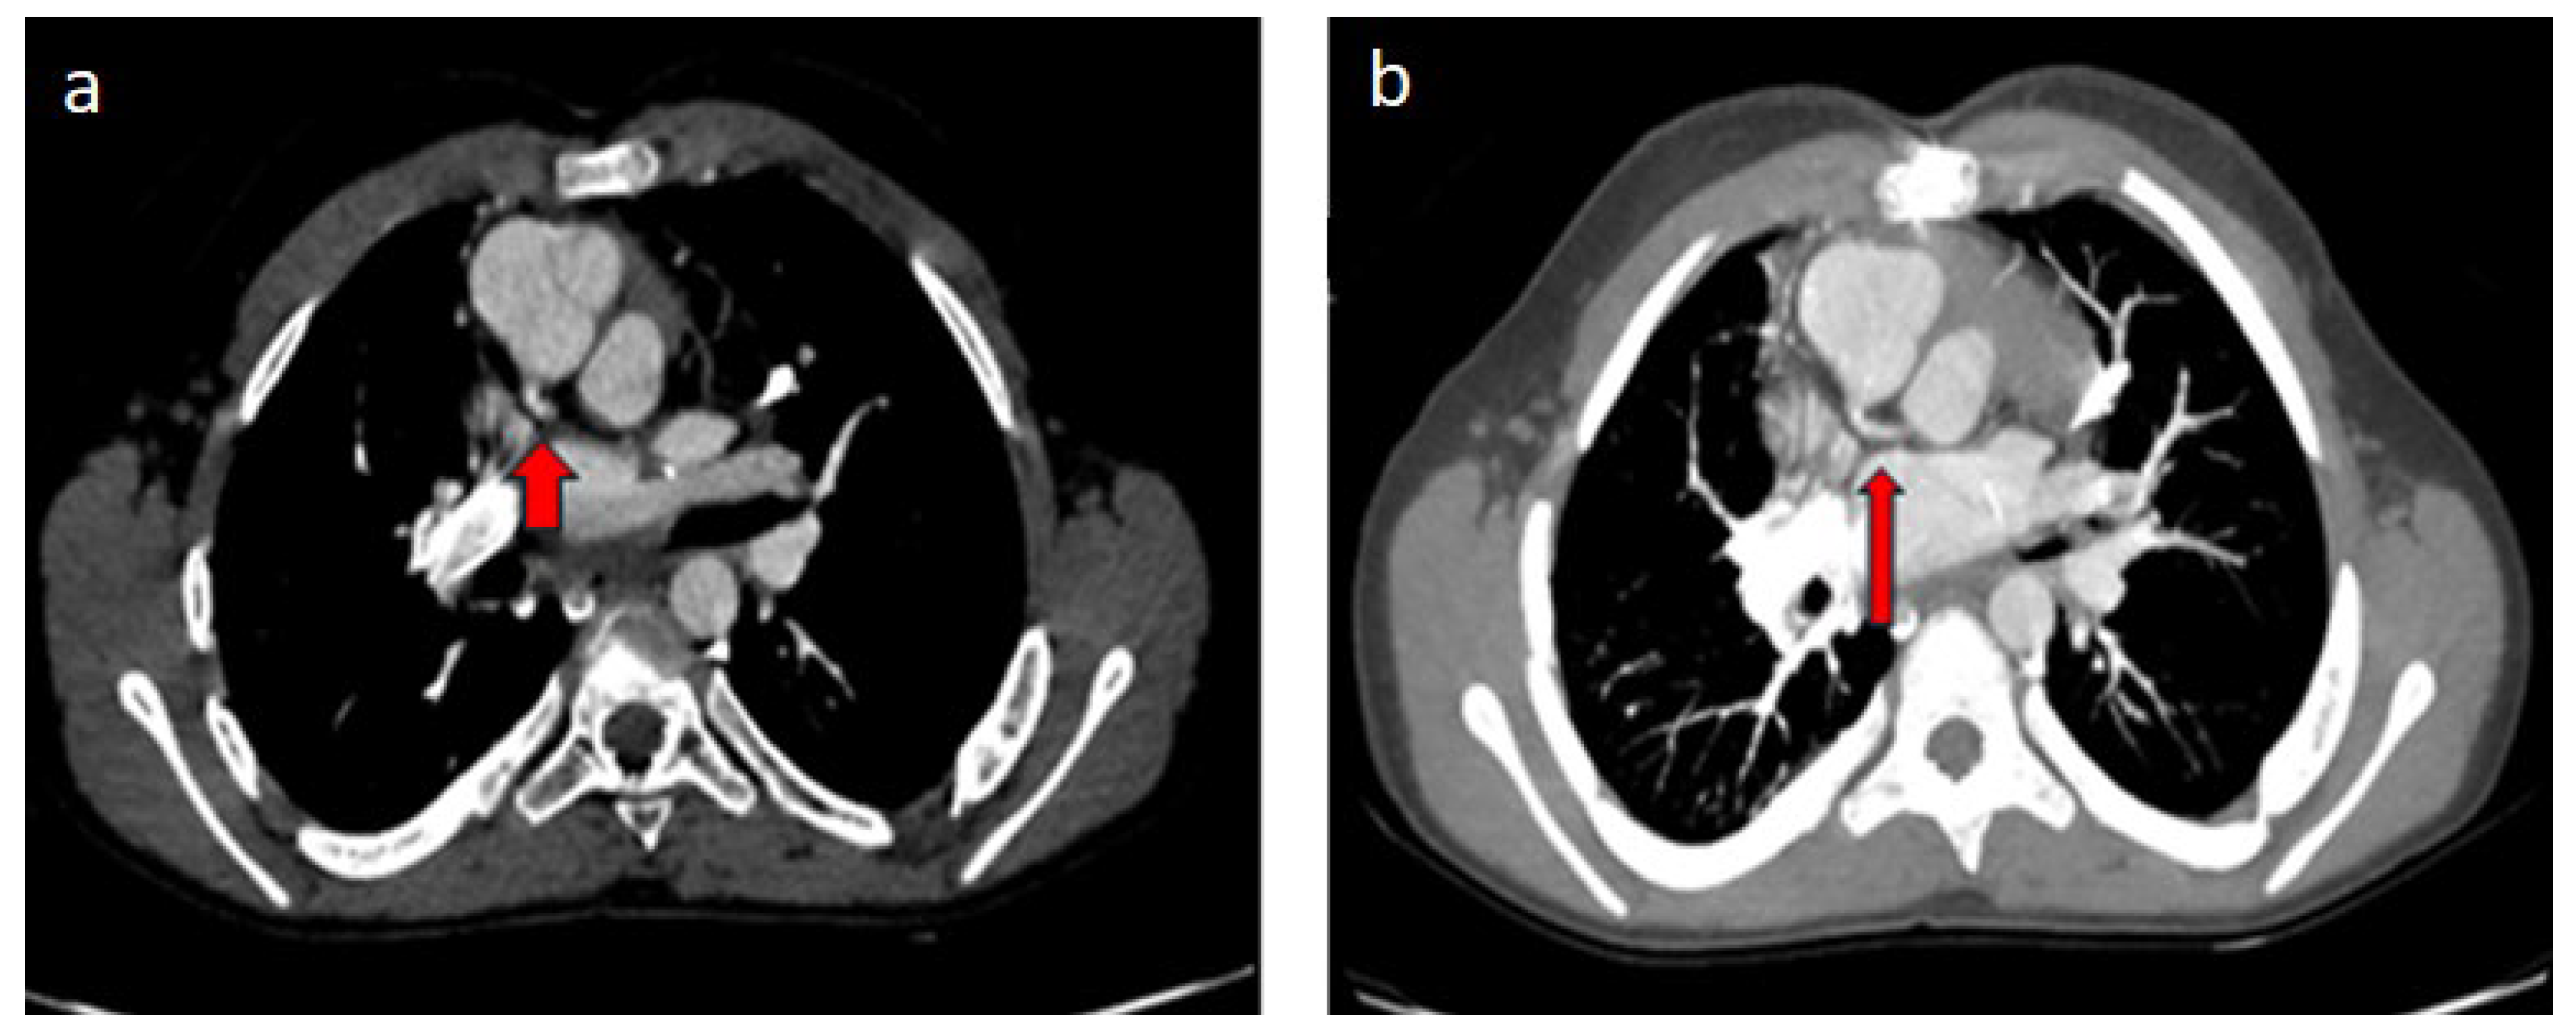

| Operated TGA (arterial switch) | Cx separated from the right coronary artery |

| Operated TGA (Rastelli) | Left coronary artery with interarterial course separated from the right coronary sinus |

| Single ventricle morphology (Fontan) | Cx leaving the right coronary sinus |

| Operated aortic stenosis, pulmonary stenosis (ROSS) | Left coronary artery leaving the right coronary sinus |